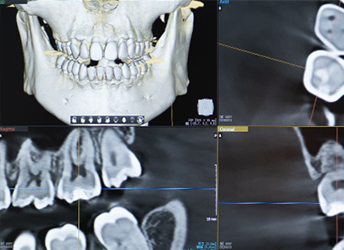

歯科用CTで、歯や顎の骨を3次元的、立体的に様々な方向から診断

通常のレントゲンでは、重なりや構造、細かい部分を見分けることが難しい場合があります。歯科用CTは3次元的に立体的な画像を撮影できますので、骨の形状や密度、神経の位置なども確認でき、診断の精度が向上し、治療の成功率も高まります。

インプラント治療の際の位置決めや、矯正治療の計画時、根管治療の際に根管の数や形の確認など、より正確な審査・診断が可能です。